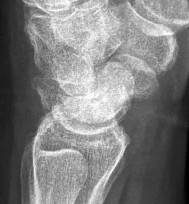

- الأشعة السينية (X-rays): هي الخطوة الأولى في تقييم الكسور، الخلوع، وتغيرات التهاب المفاصل. تساعد في تحديد مدى تدهور العظام والمسافات المفصلية. على سبيل المثال، تُظهر صور الأشعة السينية كسور السلاميات

أو كسور قاعدة العظم المشطي الخامس